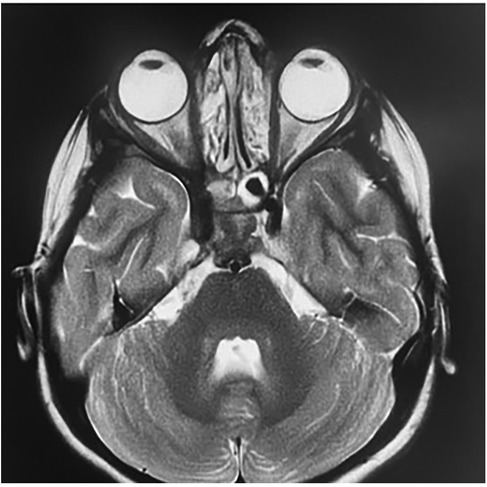

Background : Cavernous sinus tuberculosis is an extremely rare manifestation of central nervous system tuberculosis in children, with only two cases reported worldwide. It can mimic malignancy or other inflammatory conditions. Its occurrence in children with primary immunodeficiency, particularly major histocompatibility complex (MHC) class II deficiency, has not yet been described. Case report : We report an 11-year-old girl with a history of recurrent infections and chronic otitis media. She presented with right orbital swelling, severe headaches, and exophthalmos. Imaging revealed an extensive mass in the sinonasal and orbital regions, extending to the skull base and cavernous sinus. Computed tomography–guided biopsy and histopathology, supported by PCR testing for Mycobacterium tuberculosis, confirmed extensive orbital and cervicofacial tuberculosis. Immunological evaluation and genetic analysis revealed familial MHC class II deficiency. The patient received antituberculous therapy (HRZE followed by HR), leading to clinical and radiologic improvement. She continues intravenous immunoglobulin replacement every 21 days while awaiting bone marrow transplantation. Conclusions : This case highlights the importance of considering tuberculosis in atypical cavernous sinus lesions in children, especially in endemic regions. Severe or unusual infections should prompt evaluation for underlying immunodeficiency.